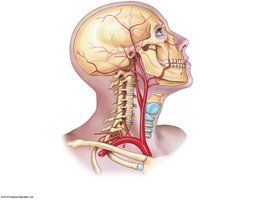

Circulation to the Brain

Blood supply to the brain is provided by the internal and external carotid arteries and vertebral arteries. The Cerebral Arterial Circle (Circle of Willis) ensures continuous blood flow to the brain.

Internal carotid → middle and anterior cerebral arteries

Vertebral arteries → basilar artery → posterior cerebral arteries

Venous Return from the Head, Neck, and Upper Limb

Blood from the head and neck drains into the internal and external jugular veins and vertebral veins, which empty into the brachiocephalic veins and then the superior vena cava. The upper limb is drained by superficial (cephalic, basilic) and deep (radial, ulnar, brachial) veins.